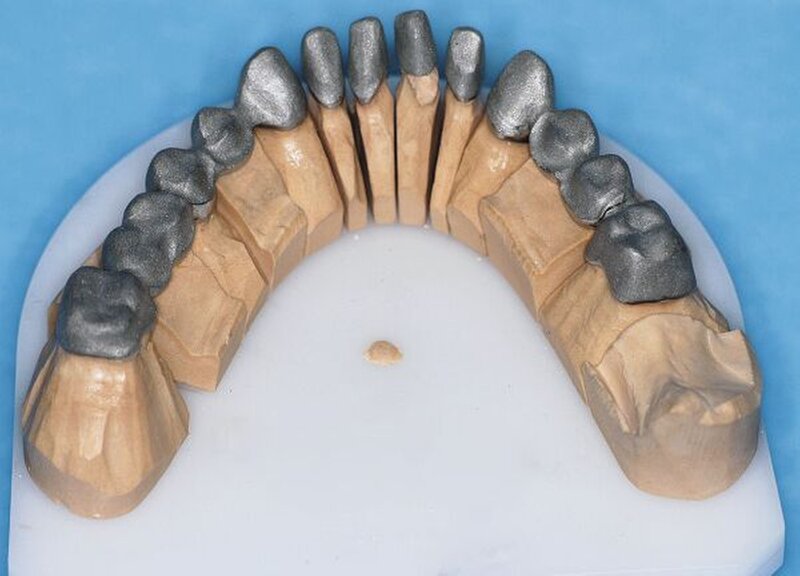

Die Abformungen des OK und des UK erfolgten als Korrekturabformung unter Verwendung eines A-Silikons. Zur Darstellung der subgingival liegenden Präparationsgrenzen wurden mit Adstringentien getränkte, geflochtene Retraktionsfäden in die Sulci aller Zähne eingelegt. Eine adäquate Trocknung der abzuformenden Bereiche wurde durch die Verwendung von Kompressions-Wattekappen, die auf den einzelnen Zähnen platziert wurden, durch Parotispflaster sowie durch eine konstante Absaugung erreicht. Um ein möglichst langes Verarbeitungsintervall zu erzielen, wurde das verwendete Silikon zuvor im Kühlschrank gelagert [Wöstmann et al., 1992; Wöstmann et al., 1999]. Nach erfolgter Abformung wurde ein Gesichtsbogen zur individuellen Übertragung des Oberkiefermodells in den Artikulator angelegt, danach wurden die Provisorien des I- und IV-Quadranten wieder befestigt. Nun wurden partielle interokklusale Registratschlüssel mithilfe eines intraoral anwendbaren Autopolymerisats im Bereich des II- und III-Quadranten angefertigt und beschliffen. In einem zweiten Schritt wurden die Provisorien im I- und IV-Quadranten entfernt und die partiellen interokklusalen Registratschlüssel des II- und III-Quadranten eingesetzt. In dieser Position wurden nun ebenfalls Registratschlüssel im I- und IV-Quadranten angefertigt und beschliffen. Durch dieses Vorgehen war es möglich, die im Rahmen der Registration ermittelte Position – unter Einbeziehung der präparierten Zahnhartsubstanz – auf die Modellsituation des Arbeitsmodells zu übertragen. Abschließend erfolgte die Farbauswahl. Die Arbeitsmodelle wurden mithilfe des zuvor angelegten Gesichtsbogens und der erstellten Registratschlüssel in einen teiljustierbaren Artikulator übertragen. Im Labor erfolgte die Herstellung der Nichtedelmetall-Gerüste der Einzelkronen 22, 32, 31, 41 und 42, die der Brücken 12 bis 21, 35 bis 37 und 43 bis 46 sowie die der Nichtedelmetall- Primärkronen 13, 14, 23 und 24.

In einer weiteren Sitzung erfolgten die Gerüstanproben der angefertigten Restaurationen. Alle Provisorien im Ober- und im Unterkiefer wurden entfernt und die präparierte Zahnhartsubstanz versäubert. Danach wurde die Passgenauigkeit der hergestellten Gerüste am Patienten überprüft. Dies erfolgte unter Verwendung einer Häckchensonde sowie eines niedrigviskösen Silikons. Zudem wurden die mechanische Stabilität, die Friktion und die technische Gestaltung überprüft.